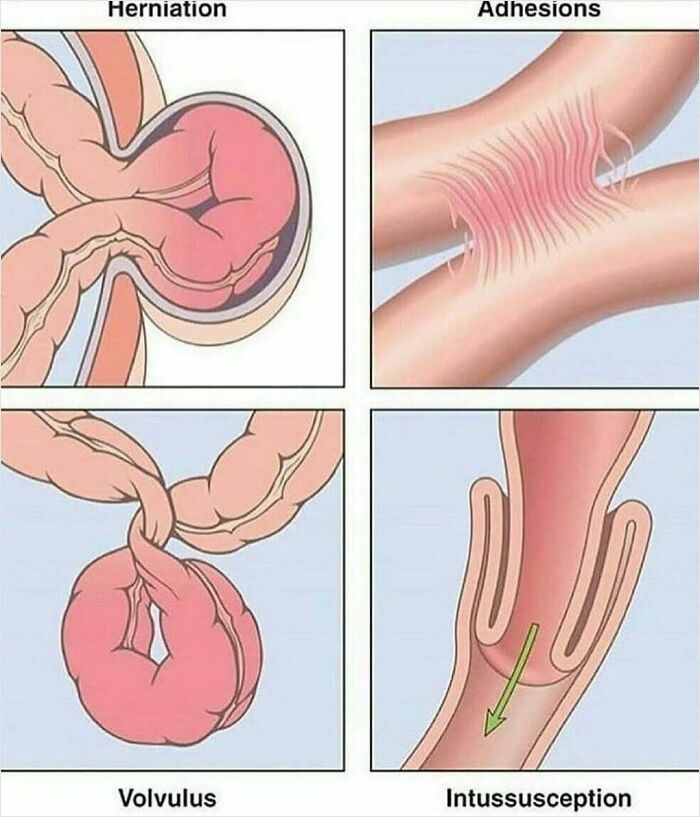

Bowel obstruction, also known as intestinal obstruction, is a mechanical or functional obstruction of the intestines which prevents the normal movement of the products of digestion. Either the small bowel or large bowel may be affected. Signs and symptoms include abdominal pain, vomiting, bloating and not passing gas. Mechanical obstruction is the cause of about 5 to 15% of cases of severe abdominal pain of sudden onset requiring admission to hospital.

Causes of bowel obstruction include adhesions, hernias, volvulus, endometriosis, inflammatory bowel disease, appendicitis, tumors, diverticulitis, ischemic bowel, tuberculosis and intussusception. Small bowel obstructions are most often due to adhesions and hernias while large bowel obstructions are most often due to tumors and volvulus. The diagnosis may be made on plain X-rays; however, CT scan is more accurate. Ultrasound or MRI may help in the diagnosis of children or pregnant women.

The condition may be treated conservatively or with surgery. Typically intravenous fluids are given, a tube is placed through the nose into the stomach to decompress the intestines, and pain medications are given. Antibiotics are often given. In small bowel obstruction about 25% require surgery. Complications may include sepsis, bowel ischemia and bowel perforation.